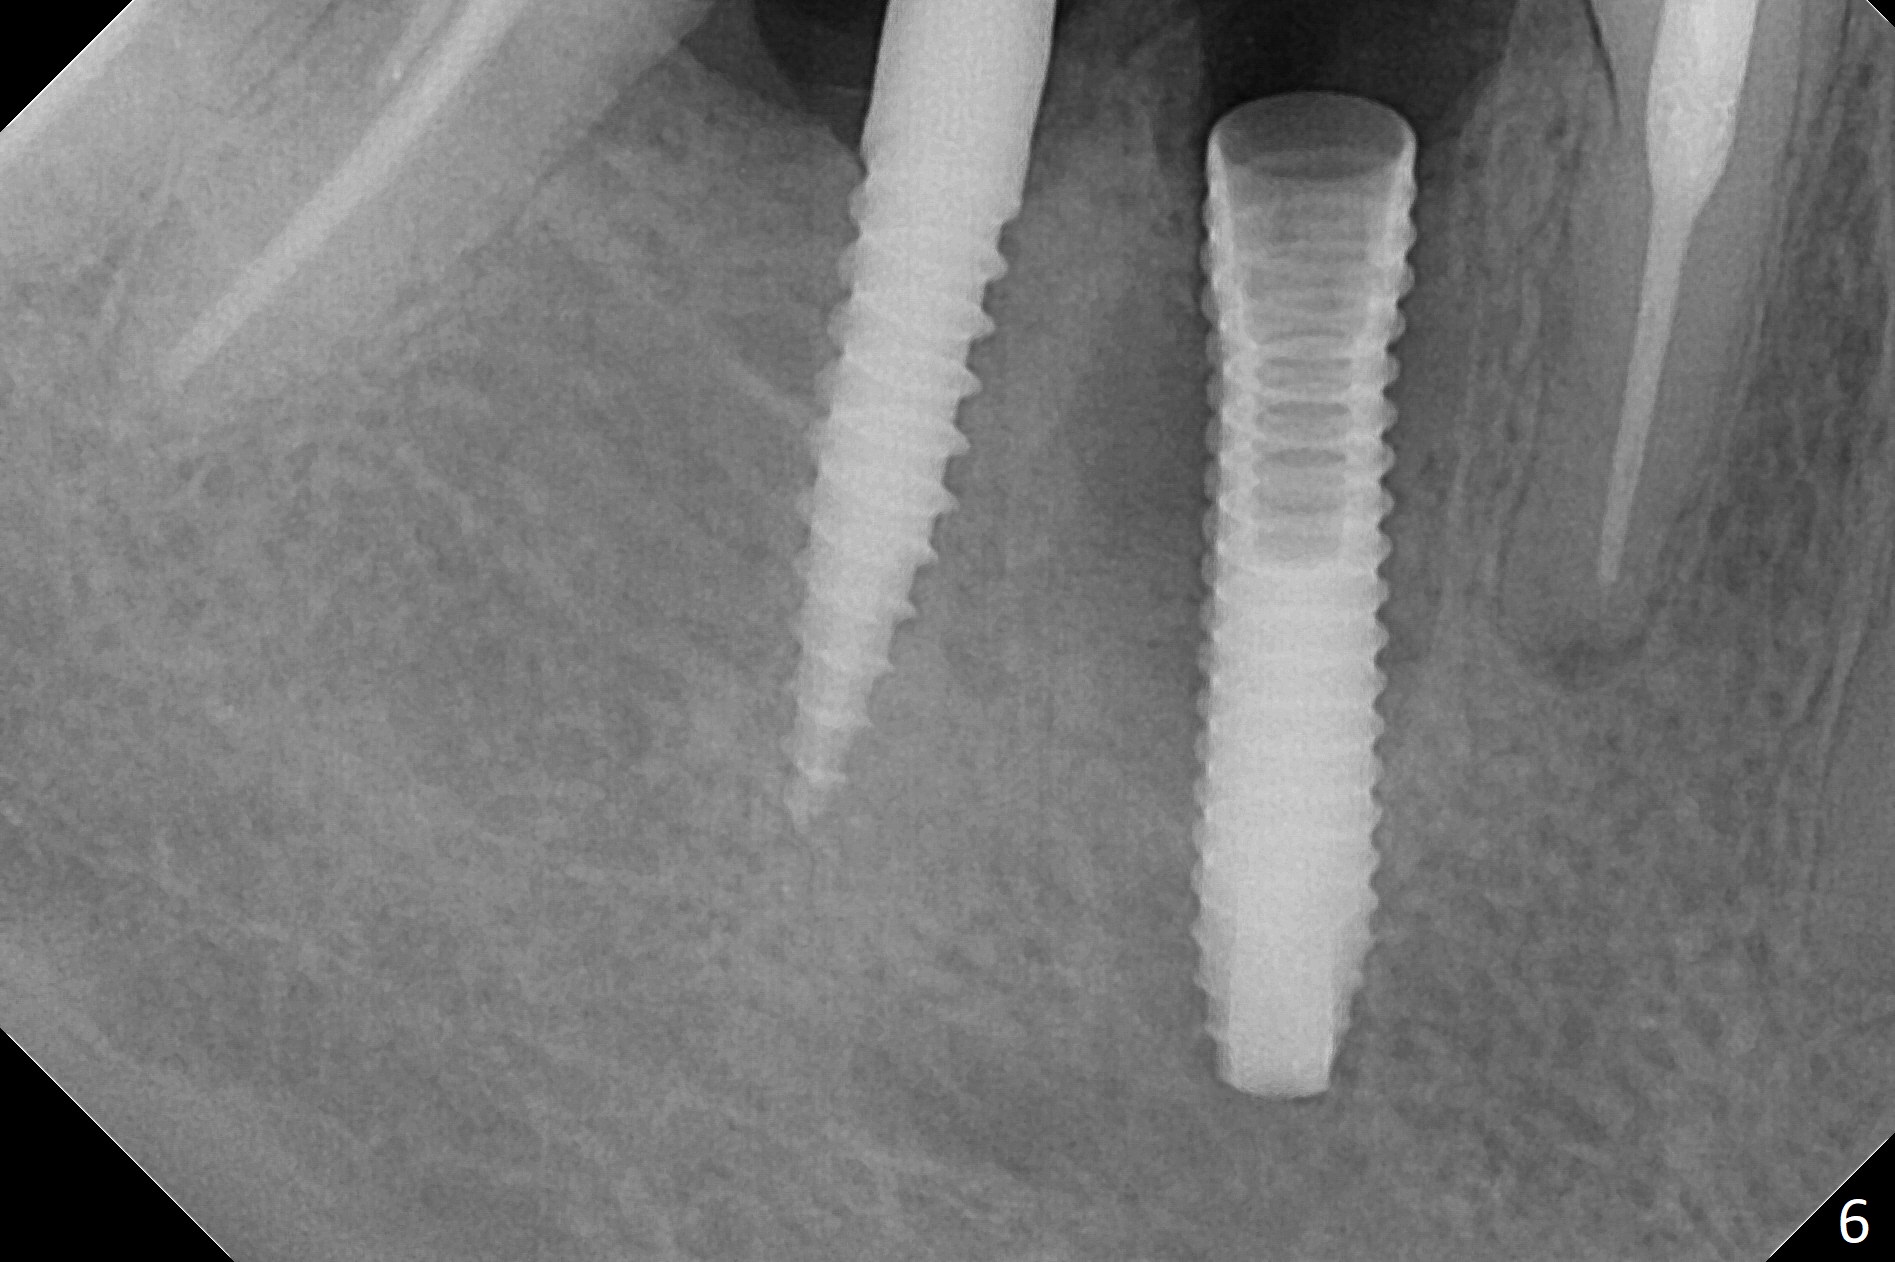

Preop examination shows that the buccal plate at #30 is atrophic (Fig.1 *). The mesiodistal width of the pontic is narrow as compared to the retainer at #31 (Fig.2). It appears that a narrow implant should be placed at #30 and should be able to sustain functional loading. After ridge reduction at #30 (Fig.3 ^) and extraction and debridement at #29, osteotomies at these sites are initiated with 1.2 mm and 2 mm drills, respectively. Probably due to low bone density, the osteotomy at #29 drops deep and close the Mental Loop (red dashed line). While the trajectory at #30 improves, the osteotomy at #29 remains close to the Mental Loop (Fig.4), asymptomatic with infiltration anesthesia. A 3x12(2) mm 1-piece implant is placed at #30 and 3.8x16 mm 2-piece implant at #29 (Fig.5,6 with insertion torque >50 and <50 Ncm, respectively). The large distal defect at #29 (Fig.3,5 *, most likely due to post-related perforation) is later filled with bone graft (data not shown). After placing an abutment at #29 and suturing, periodontal dressing is applied. Three months later, the meisal gap of #29 disappears while the distal one reduces (Fig.7 *). The abutment is changed to 4.5x4(4) mm one before reprep for impression. There is no bone loss 9 months post cementation (Fig.8) or 3 years 9 months post cementation (Fig.9). In fact the crown is lost at #31. At repeated request from the patient, a prefabricated post and crown will be fabricated for short term purpose while an implant is going to be placed at #19. The new crown at #31 has no occlusal contact (Fig.10), which may change over time.